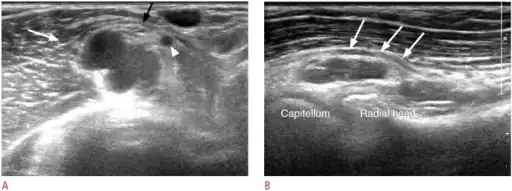

| The supinator. (Deep branch of radial nerve labeled at upper right and lower right. Dorsal interosseous is this nerve after passing the supinator, at lower right.) | |